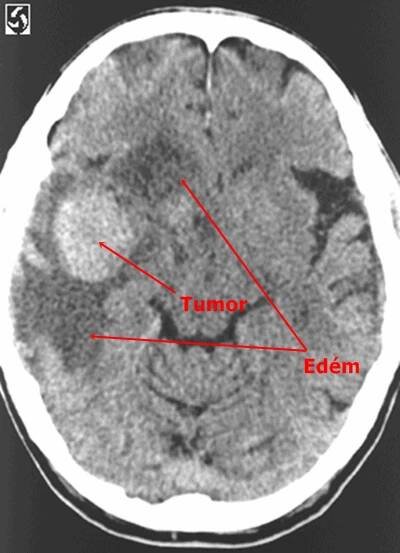

Perifokální edém mozku - CT | Medicína, nemoci, studium na 1. LF UK

Edém mozku je obvykle rozdělován do dvou typů: vazogenní a cytotoxický. Rozvoj vazogenního edému mozku je spojen s poškozením hematoencefalické bariéry.

Otok mozku (mozkový edém) je specifickým otokem části těla. Ostatní oteklé orgány či tkáně se mohou relativně volně zvětšit, mozek je však uzavřen v lebce, a proto je jeho otok spojen s nebezpečným zvýšením nitrolebního tlaku.